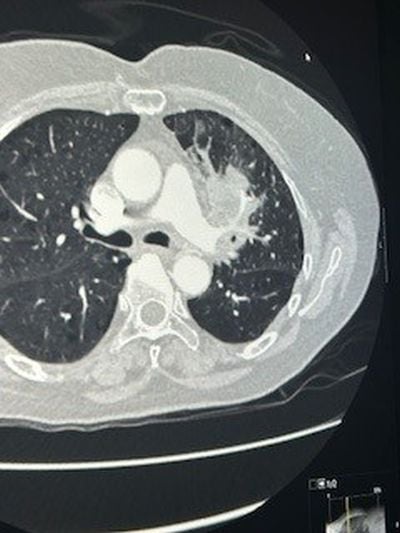

Στις φωτογραφίες 1 και 2 φαίνεται μεγάλος όγκος αριστερού πνεύμονος που εμφάνισε απόστημα και σηψαιμία. Οι λεμφαδένες που κατεγράφησαν στην αξονική και στο Pet Scan χαρακτηρίστηκαν καρκινικοί λεμφαδένες και το περιστατικό είχε χαρακτηριστεί ανεγχείρητο. Μια γενναία απόφαση της ομάδας μας, οδήγησε τον ασθενή σε αριστερή πνευμονεκτομή, όλοι οι λεμφαδένες ήταν αρνητικοί για κακοήθεια (ήταν έντονα φλεγμονώδεις και έδιναν ψευδή εικόνα) και κανένα από τα υπόλοιπα όργανα δεν είχαν διηθηθεί παρά τη γειτνίαση με τον όγκο (αορτή, μεσοθωράκιο, τραχεία). Η ασθενής είναι σε άριστη κατάσταση και είναι σε πρώτο κύκλο χημειοθεραπείας.